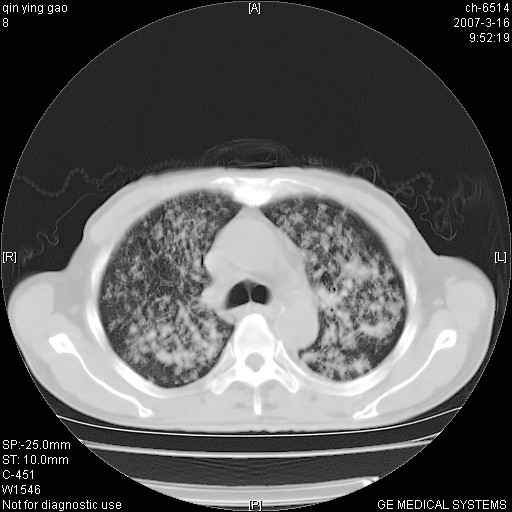

男,64岁.乏力2个月,畏寒、发热1月余。体重下降。血沉加快,白细胞不高。

两中上肺见有广泛新老不一的结节灶,并伴有纤维索条影,血沉加快,白细胞不高,首先考虑结核。

双肺可见大小不等结节状密度增高影,密度不均,分布不均(双肺上叶为著),亚急性血行播散性肺结核.

(本例特征:以大小不等结节为主,主要分布在双上肺,并部分病灶融合成较大结节,期间搀杂诸多细小结节。从病灶特点与分布形式分析,更趋向于感染。)

男,64岁.乏力2个月,畏寒、发热1月余。体重下降。血沉加快,白细胞不高。 双肺可见大小不等结节状密度增高影,密度不均,分布不均(双肺上叶为著),亚急性血行播散性肺结核.

以双肺上叶为主的弥漫型斑片状密度增高影,边界欠清晰,其中伴有钙化灶,病人有发热史,首先考虑感染性病变:1特殊类型感染,2结核。建议治疗后随诊复查,除外肺泡癌

两中上肺见有广泛分布大小不一的结节灶及斑片状影,部分融合,双下肺未见异常密度影,纵隔无明显肿大淋巴结,血沉加快,白细胞不高,首先考虑结核。 建议结合ppd检查或痰培养排除其他非特异性炎症。

中上肺野密布棉团状影,以胸膜下区为界,边缘模糊,可能是小叶或腺泡渗出及实变。全肺野弥漫分布网线样影及细小粟粒样影,可能是细支气管炎及间质内炎症。综合分析应首先考虑气道播散性感染,而肺内多处斑点性钙化,强烈提示陈旧结核复发并支气管播散。建议详细讯问病史

病变以两肺上野为著,部分病灶有钙化,纵隔窗显示病灶有新老不一,这个首先和结核脱不了干系,还有部分病灶有融洽的倾向,肿瘤也不能完全排出